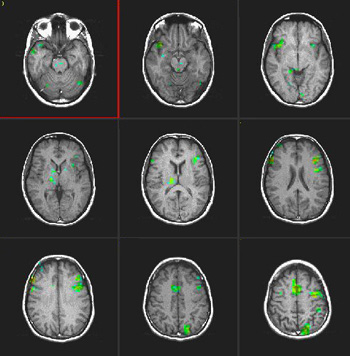

| Activación |

La activación del hemisferio izquierdo es claramente mayor. La activación se encuentra en las siguientes áreas: Área de Broca (imagen 5), área de Wernicke (imágenes 4 y 5), circunvolución supramarginal izquierda (área de asociación heteromodal, imagen 5), corteza motora y premotora izquierda. Las áreas auditivas primarias también están activadas, predominantemente en el lado izquierdo. |